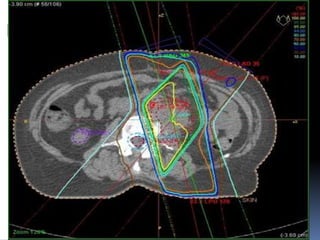

 The finished plan has iso-dose curves to show

which areas are receiving what dose (amount) of

radiation.They are very similar to traditional

weather maps to show the low and high pressure

systems.

 Area the clinical oncologist wishes to treat is

outlined in red dotted marks .

 The other lines represent the dose of radiation the

patient will receive .

 The yellow line represents 100% of the dose and the

dark green line represents 98% of the dose.

 The right kidney (outlined in purple on the left of the

image) receives no dose.

